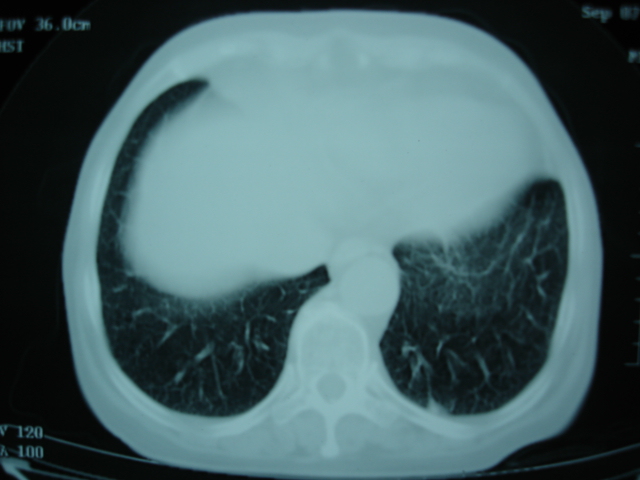

以下是引用卜一在2009-9-7 19:51:00的发言:[br][br] 1 左侧胸内甲状腺占位-多考虑甲状腺腺瘤! 2、左肺门占位-建议增强扫描以便明确性质。 3 慢支并感染! [br]

以下是引用shibing在2009-9-7 20:40:00的发言:[br]左侧胸内甲状腺占位-多考虑甲状腺腺瘤! 2、左肺门占位-建议增强扫描以便明确性质。 3 慢支并感染! [br]